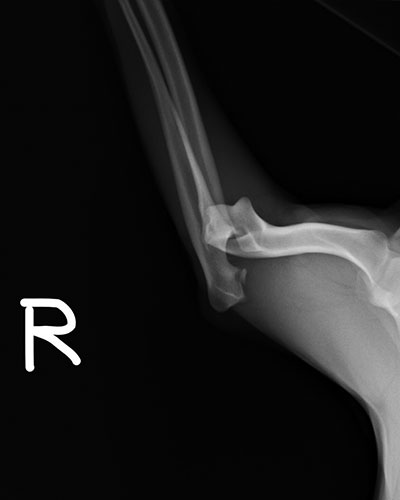

右肘關節脫位

不慎被車子撞到的NONO,經X光診斷發現右肘關節脫位,施行人工韌帶固定術後目前已可恢復行走。

術前